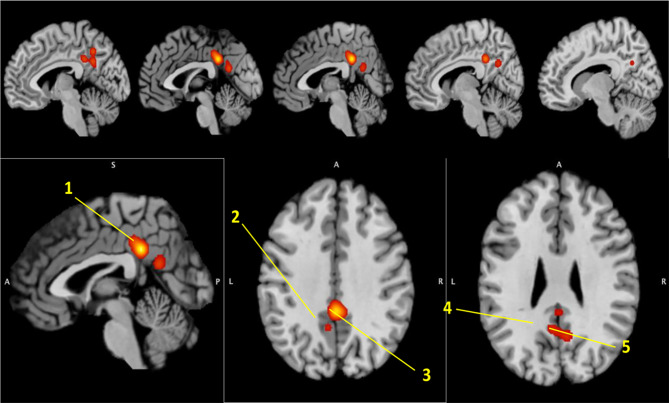

Several recent reviews have evaluated amalgamated evidence obtained from fMRI studies of tinnitus [38, 71]. Overall evidence suggests resting-state alterations primarily in the default-mode, auditory, and attention resting-state networks, as well as the visual network. Specific findings, however, such as exact loci of these alterations and directionality of the results (whether connectivity increases or decreases) often show conflicting or oppositional findings and lead to inconsistent conclusions. One may suspect that this might be an inherent flaw within the tool itself, but recent work has shown resting-state fMRI (specifically seed-to-seed resting state functional connectivity) to be a robust measure, both within people with tinnitus and controls, on both a short-term as well as a long-term [70]. This naturally suggests another source for this variability, which is commonly thought to be both the inherent heterogeneity in the tinnitus population, as well as variance in the study populations due to poor controls or insufficient power. Various neuroimaging studies of tinnitus do not sufficiently control for comorbid factors of the tinnitus experience (such as hearing loss, aging, or other hearing conditions such as hyperacusis) and often contain relatively small sample sizes. PET studies were one of the first brain imaging studies to identify large-scale neural networks subserving tinnitus. Over the years, the number of PET studies has been overtaken by the more ubiquitous fMRI tool, but nevertheless, the pioneering PET studies have paved the way for our understanding of tinnitus in humans. The initial rest-based studies using PET often had few participants or focused on specific regions such as the auditory cortex. A few studies attempted to estimate any asymmetry in regional cerebral blood flow measures (estimate of neural activity) in the auditory cortices [72–75] but found some contradictory results. While earlier studies noted an asymmetry in the auditory cortex regional cerebral blood flow in tinnitus patients, Geven et al. [73] also noted a similar asymmetry in controls. Thus, a promising lead on hyperactivity in the auditory cortex as a neural correlate of tinnitus did not pan out. In recent work from our lab [76], we estimated the global perfusion in the brain of 10 tinnitus patients and controls using arterial spin labeling, an analog of PET’s regional cerebral blood flow measure using MRI. The global cerebral blood flow was found to be reduced in tinnitus, with this reduction correlated with severity of tinnitus symptoms. A ROI analysis also saw reduction in the blood flow in the precuneus and posterior cingulate cortex, but not in the posterior superior temporal gyrus or the dorsomedial frontal gyrus, other regions tested, in the tinnitus group compared to controls. This reduction was separately correlated with both hearing loss and tinnitus severity. In an innovative effort to integrate both structural and functional bases of tinnitus, a recent meta-analysis implemented activation likelihood estimation (ALE) on a total of 17 resting-state fMRI and 7 VBM studies of tinnitus [77]. The authors found a significant cluster comprising the posterior cingulate cortex and precuneus (Fig. 1 in this paper). This led the authors to conclude that tinnitus likely impacts a wide range of neural connections, and is not simply limited to auditory processing regions.

Fig. 1.

Regions identified by corrected ALE. Note: 1, cingulate gyrus; 2, precuneus; 3, cingulate gyrus/precuneus; 4, posterior cingulate/precuneus; 5, posterior cingulate/precuneus. From Moring JC, Husain FT, Gray J, Franklin C, Peterson AL, Resick PA, Fox PT (2022) Invariant structural and functional brain regions associated with tinnitus: A meta-analysis. PloS ONE 17(10):e0276140; Figure 2 [77]